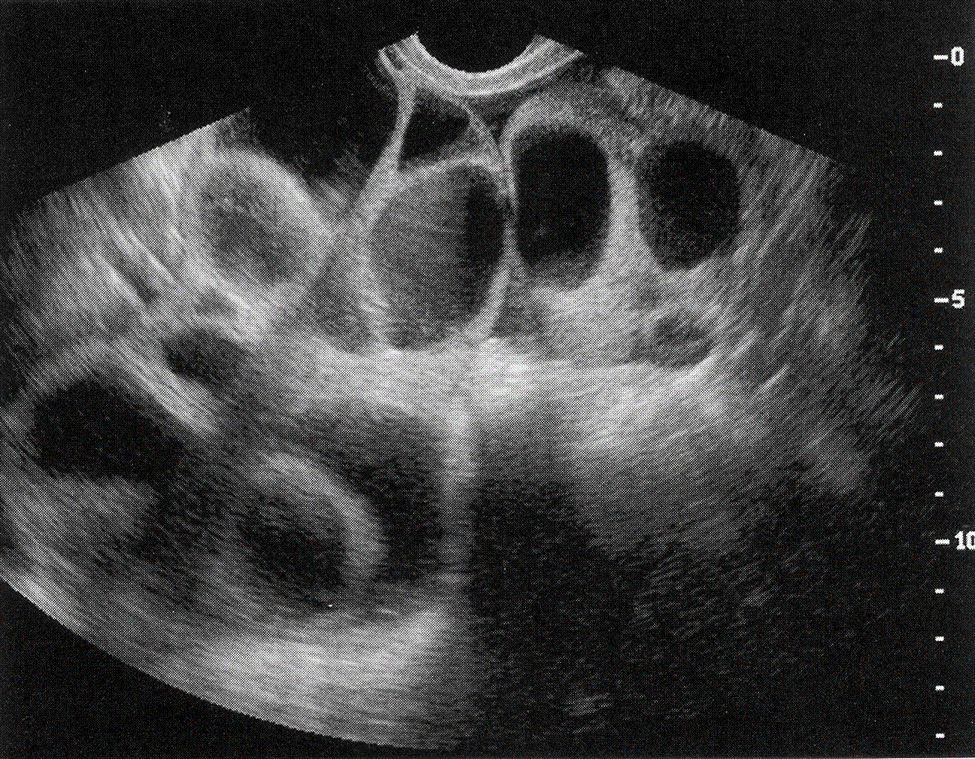

Follicles

Polycystic Ovarian Syndrome“string of pearls”

ovarian volume > 10 cm3

peritoneal inclusion cysts